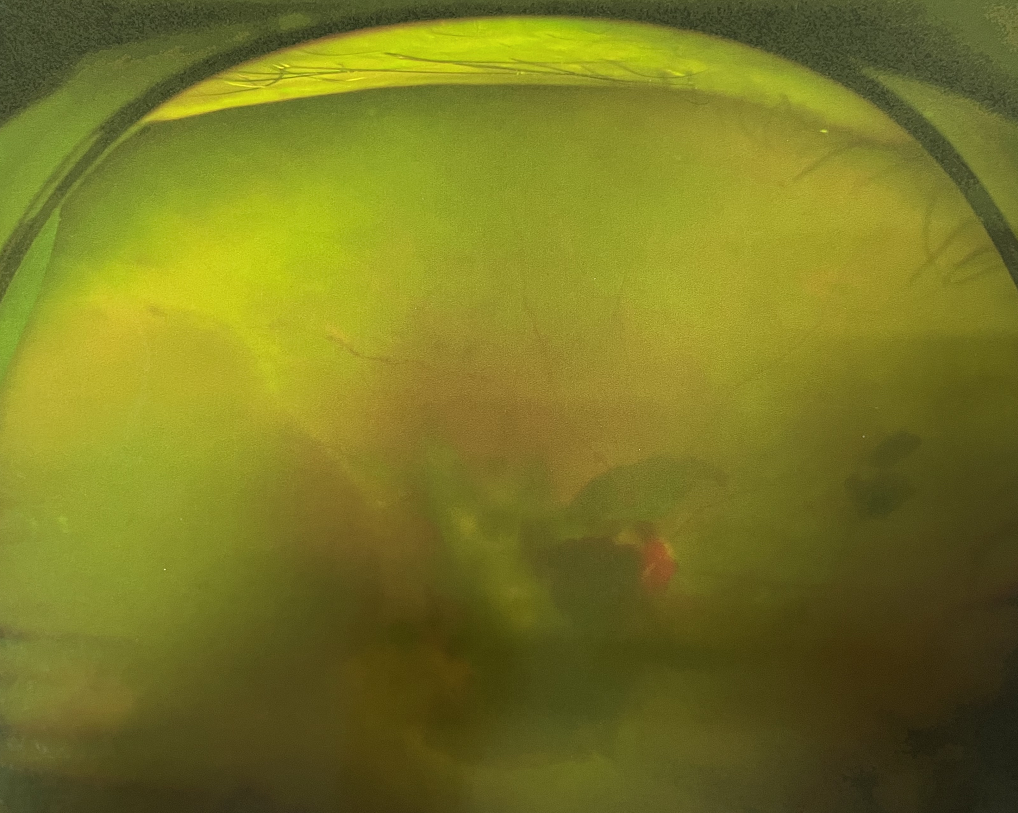

眼底出血多指玻璃體內(nèi),眼睛更深處的視網(wǎng)膜出血。通常情況下,肉眼難以發(fā)現(xiàn)眼底出血,而且發(fā)病初期眼睛也無(wú)明顯癥狀,只有借助專(zhuān)業(yè)的眼底檢查儀器才能觀察到異樣。那么眼底出血嚴(yán)重嗎?

誘發(fā)眼底出血的原因眾多,常見(jiàn)的有全身性血管病和血液病、視網(wǎng)膜血管異常、機(jī)械性阻塞、炎癥性疾病或免疫復(fù)合物侵犯血管壁等。

眼底出血嚴(yán)重嗎?其中,“三高”患者、高度近視患者和滲出性或濕性老年黃斑變性患者是眼底出血的高發(fā)人群。

眼底出血嚴(yán)重嗎

眼底出血嚴(yán)重嗎?對(duì)于已出現(xiàn)黃斑水腫、視網(wǎng)膜新生血管的患者,根據(jù)眼底血管造影、oct等檢查結(jié)果,給予玻璃體腔注射抗VEGF藥物及激光治療,可以減輕黃斑水腫,使視網(wǎng)膜新生血管消退,以免進(jìn)一步發(fā)生玻璃體出血、視網(wǎng)膜脫離等嚴(yán)重并發(fā)癥的出現(xiàn)。對(duì)于玻璃體出血者,傳統(tǒng)認(rèn)為玻璃體出血3-6個(gè)月不吸收再進(jìn)行手術(shù)干預(yù),但近年來(lái)因?yàn)轱@微手術(shù)設(shè)備及玻璃體切割技術(shù)已非常成熟,故對(duì)于1個(gè)月不吸收的玻璃體出血者就可以考慮手術(shù),即手術(shù)時(shí)機(jī)應(yīng)該具體情況具體分析,因人而異。